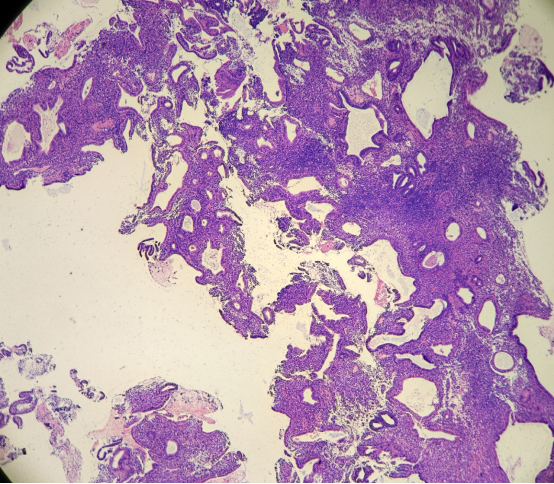

3. 与分泌性子宫内膜及分泌型AH/EIN的区分

AH/EIN有时可伴有分泌性改变,称为分泌型AH/EIN。其组织学上保留了经典AH/EIN的部分特征(如腺体排列杂乱、结构复杂),同时可见分泌期样改变(如胞质丰富透明、核下空泡等)。正常的分泌期子宫内膜虽然腺体也可拥挤、弯曲,甚至呈锯齿状,但腺体排列相对规则,细胞有极性。而分泌型AH/EIN的腺体拥挤和结构复杂程度通常更显著,排列更不规则。免疫组化Ki-67的表达有助于鉴别,分泌型AH/EIN的Ki-67指数通常明显高于背景分泌性内膜。

图示:伴有分泌改变的AH/EIN,腺体密集拥挤,排列不规则,可见核下空泡(绿色虚线)和管腔分泌物(红色虚线),但细胞层次增多、极性紊乱及核非典型性支持AH/EIN诊断。

a:分泌型AH/EIN,腺体密集拥挤,细胞层次多,极性乱; b:背景分泌性子宫内膜,腺体稀疏,细胞单层,排列整齐。